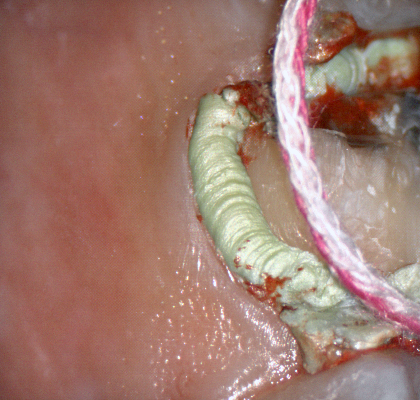

A shoulder bur of .8 mm thickness can help you reduce the interproximal areas as well as the buccal and lingual margin lines. Before finishing the prep, place hemostatic agent like expasyl in the sulcus and place retraction cord. while it is setting, check your reduction. If you need more space, now is the time to reduce some more.